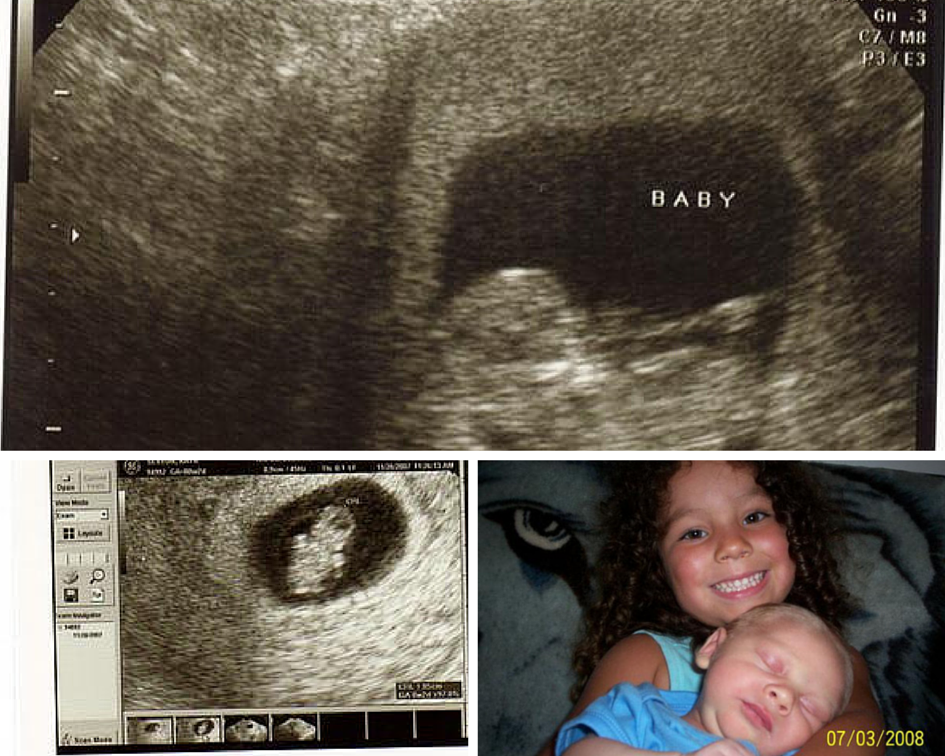

With Mothers Day just days away, I find myself thinking back, thinking back to those times where becoming a mother was just the beginning of my journey into motherhood. When my husband and I were first married, I had already had my daughter from a previous relationship. So I was already a mom, but I was a mom who was ready to embark on a new journey, the one of becoming a family with my husband and adding to our new family. I can remember when we were ready to get pregnant, it was all I could think of. We had a loss just a few months prior, and due to the loss and complications I had, I was going in regularly to my OB because we were told that there was concern over the fact on whether or not we could get pregnant again.

We were ecstatic, and when we went in for our next appointment that following week, the Dr confirmed the results we got from our Clearblue Pregnancy Test, making the moment when we found we were having our middle child, a moment we will never forget! So if you are trying to get pregnant or you think you might be pregnant, keep the products from Clearblue in mind when it comes to that special time in your life!